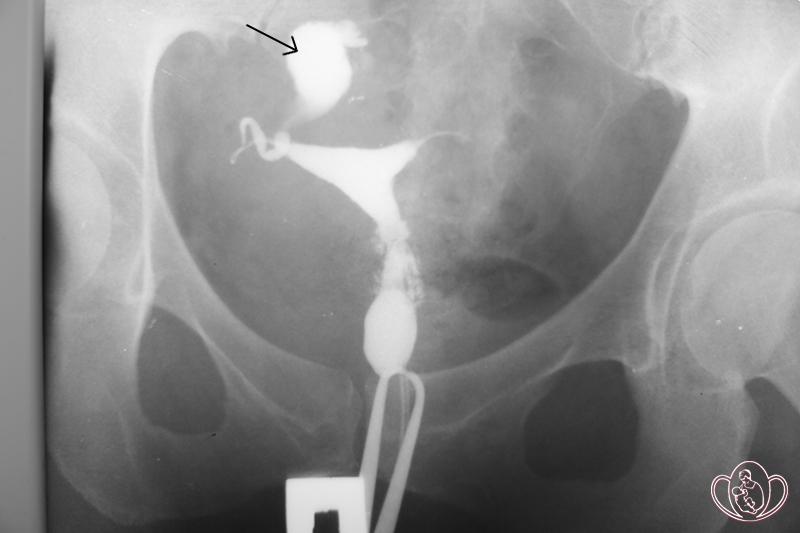

Гистеросальпингография (ГСГ) — это рентгенологическое исследование матки и труб, которое позволяет получить объективную информацию об их состоянии, позволяет оценить проходимость и функциональное состояние маточных труб, рельеф и размер слизистой оболочки матки.

| Контроль проходимости маточных труб под рентгенологическим контролем. Определяется правый сактосальпинкс. Сактосальпинкс обозначен стрелкой. Зубцы пулевого зажима видны внизу изображения | ![]() |